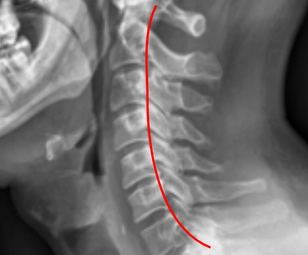

Image Type Cervical Spine X-Ray CT Scan MRI Scan Atlantodental Interval (ADI) Basion-Axial Interval Basion-Dens Interval (BDI) C2 Tilt C2–C7 Coronal Cobb Angle Cervical C2-7 lordosis C2-C7 Translation Chamberlain’s Line / McGregor’s Line Flexion-Extension George’s Line (Posterior Cervical Line) K-Line Interpedicular Distance (IPD) Occiput-C2 Angle Occipital Condyle–C1 Interval (CCI) Posterior Atlantodental Interval (PADI) Power’s ratio Sagittal Canal Diameter Sagittal Vertical Axis (SVA) Spinolaminar line Swischuk Line T1 Slope Torg/Pavlov Canal-to-Body Ratio